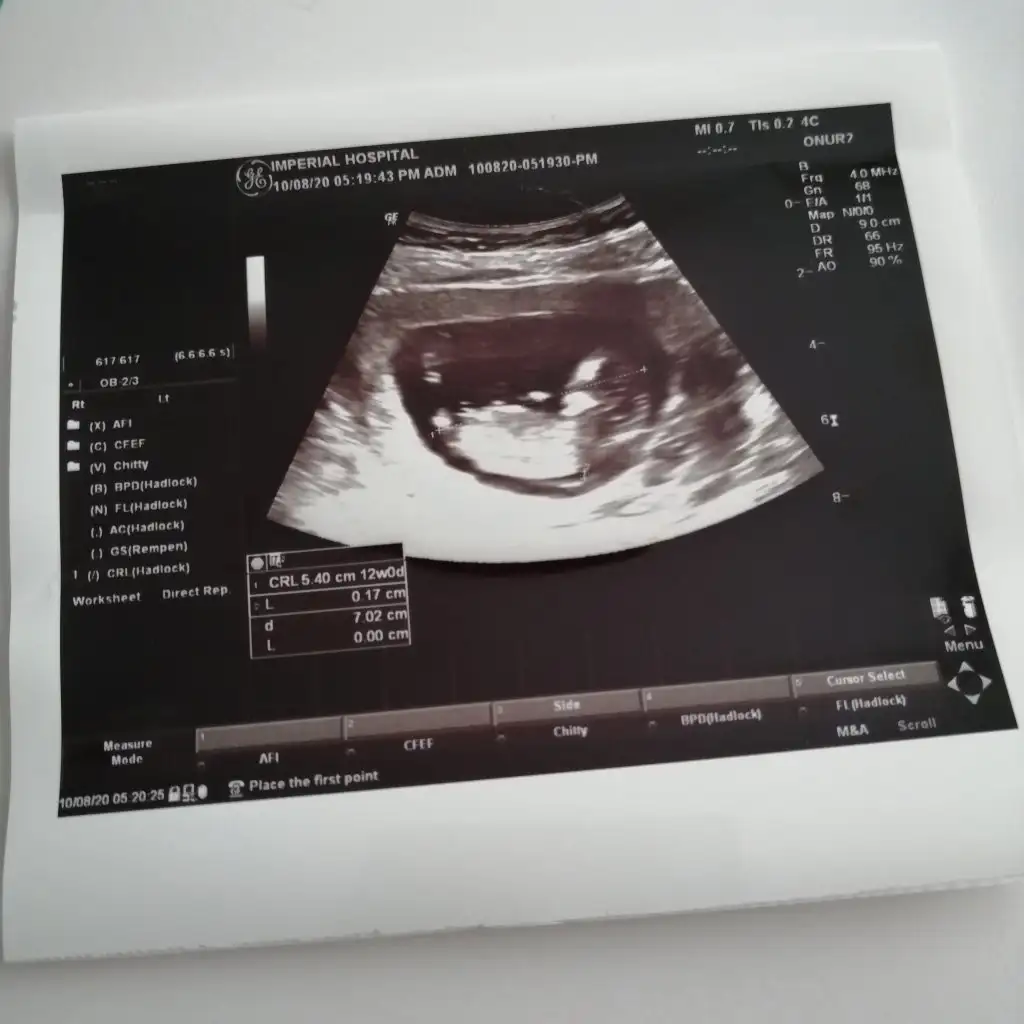

Ben bebeğimin cinsiyetini biliyorum tabi sonradan bir sürpriz çıkmazsa.. :) ama bahsettiğiniz o çıkıntı ya bakıyorum (11 ve 12. Haftalara ait birden çok usg görüntüsü var elimde) bazılarında çıkıntı kıza işaret ediyor bazılarında ise erkeğe :)Erkek ve kız için 11 yada 12 hafta usg görüntüsü olmalı açıklamalar asagıda yazıyorrabbim herkesin gönlüne göre nasip etsin inşallah .. ecmain

[/B]Eki Görüntüle 473828 gordugunuz gibi ust taraftaki simgedende anlasildigi gibi eger cikinti paralel ise kiz

yok 30°lik bir aciyla yukari dogru bakiyorsa %99 oglunuz olacak demektir simdi bi kac ornek resimler daha koyacagim kiziminkide dahil

Eki Görüntüle 473829 bu bir erkek bebek genital nub cikintisi gayet yukarda

Eki Görüntüle 473831 simdi burada cikintilara bakin eger bel popo cizgisine paralel ise kiz

yok 30 derecelik bir aciyla yukari bakiyorsa erkek

yabancilarin hepsi biliyor bunu biz neden eksik kalalim gayet bilimsel simdi ellerinde11 12 13 ultrason fotografi olanlar alsin hemen baksin yada koyalim buraya yorumlayalim